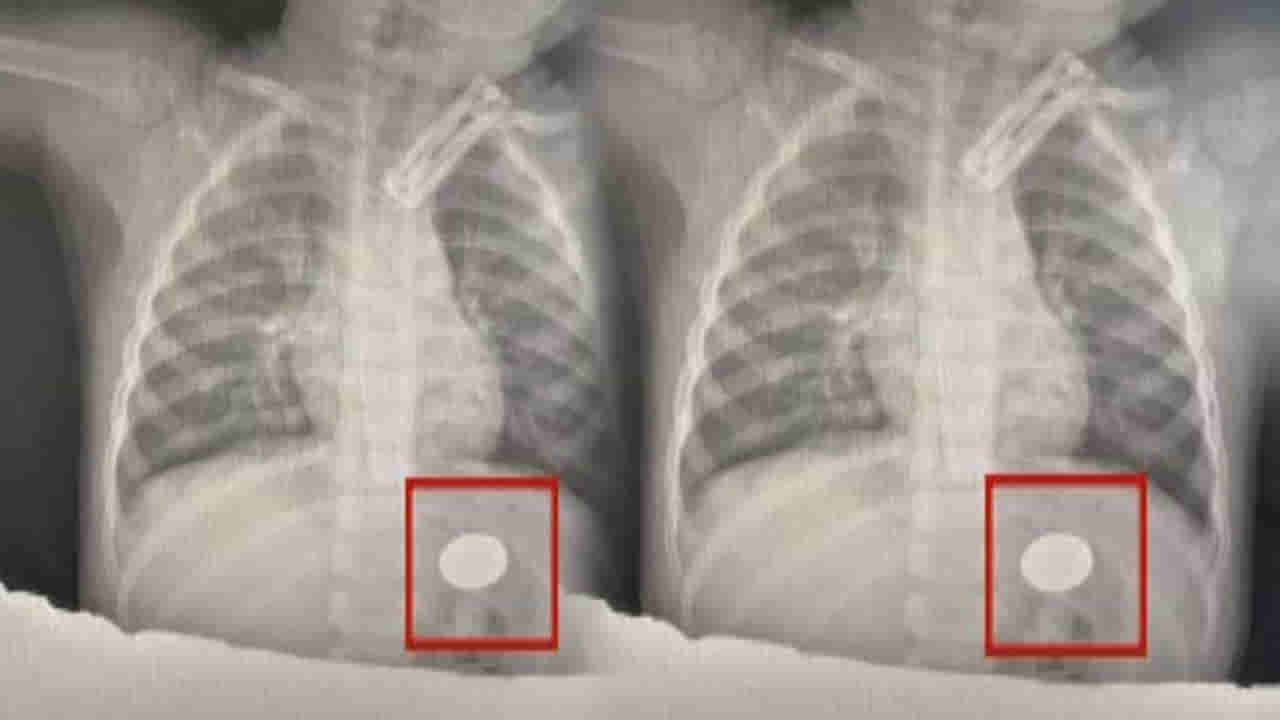

తూర్పు చైనాలోని జియాంగ్సు ప్రావిన్స్లోని లియాన్యుంగాంగ్లో ఓ వైద్యుడు.. ఏడాదిన్నర వయస్సు ఉన్న చిన్నారి ఛాతీ ఎక్స్రే చూసి కంగుతిన్నాడు. ఆ చిన్నారి జీర్ణవ్యవస్థ పైభాగంలో ఒక నాణెం ఉన్నట్లు గుర్తించారు. ఆ నాణెం అప్పటికే నల్లగా మారిపోయిందని.. అది శరీరంలో నెల రోజులకు పైగా ఉన్నట్టు డాక్టర్లు తేల్చారు.

న్యుమోనియా చికిత్స నిమిత్తం ఆ చిన్నారి మొదటిగా ఆస్పత్రిలో చేరిందట. వికారం, వాంతులు, పరోక్సిస్మల్ ఏడుపు వంటి లక్షణాలను ఆ చిన్నారిలో తల్లిదండ్రులు ఏం గుర్తించలేదని డాక్టర్లు చెప్పారు. చిన్నారిది చిన్న వయస్సు కావడం అలాగే.. గ్యాస్ట్రిక్ కుహరంలో విదేశీ వస్తువు ఉండటం వల్ల సహజంగానే అది బయటకు వెళ్లే అవకాశం లేదని డాక్టర్ గుర్తించారు. బిడ్డ ఆరోగ్య పరిస్థితిని దృష్టిలో పెట్టుకుని.. దాన్ని త్వరతగిన శస్త్రచికిత్స ద్వారా తొలగించాలని డాక్టర్లు భావించారు.

అయితే మొదటిగా జీర్ణశయాంతర ఎండోస్కోపీ నిర్వహించేందుకు ఆ చిన్నారి తల్లిదండ్రులు ఒప్పుకోలేదని డాక్టర్లు అన్నారు. కానీ సెకండ్ విజిట్లో చిన్నారికి ఆపరేషన్ నిర్వహించారు. ఆ చిన్నారి వయస్సును దృష్టిలో పెట్టుకుని చాలా టెక్నికల్గా ఆ నాణాన్ని కేవలం 10 నిమిషాల్లోనే బయటకు తీశారు.